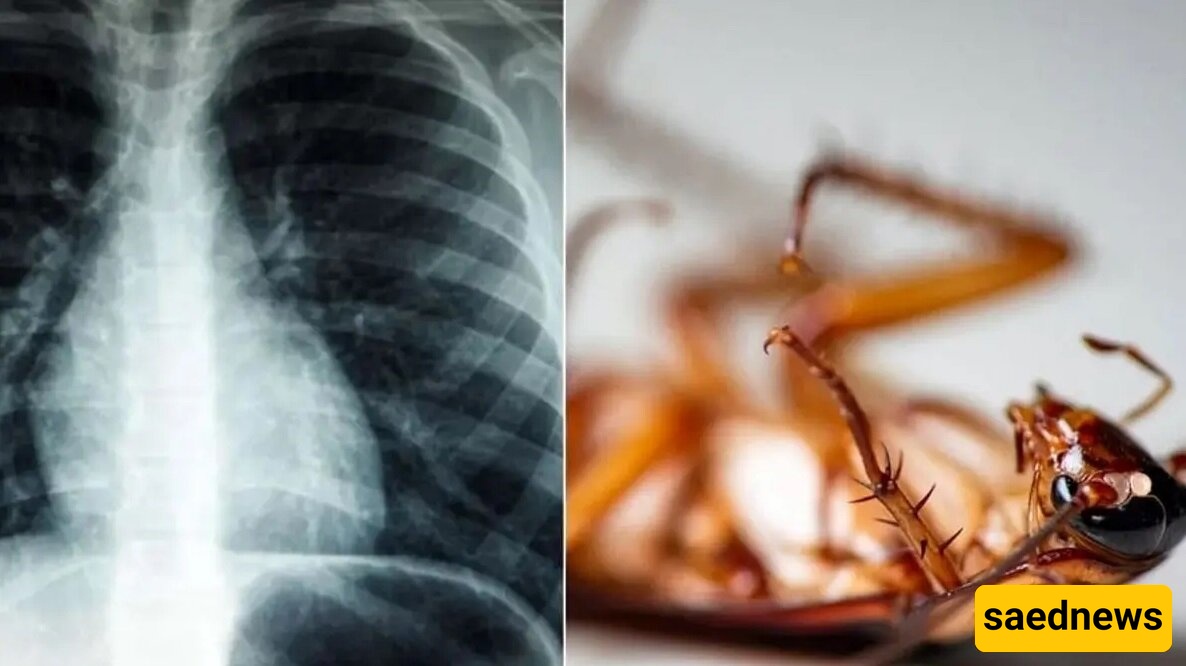

Removing a 4-Centimeter Live Cockroach from the Lung of a 55-Year-Old Man

According to Saed News’ social affairs report, citing Hamshahri, a 55-year-old man visited a hospital in Kerala, India, reporting that he was feeling unwell. Respiratory issues prompted doctors to perform a bronchoscopy, during which they discovered a four-centimeter cockroach inside his lung.

Doctors suggest that the insect likely entered his lung through a tube that had previously been inserted in his throat to deliver oxygen.